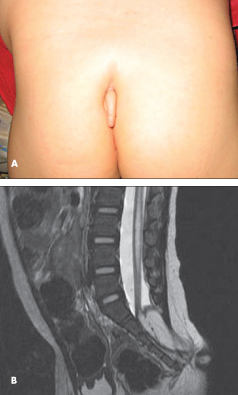

A 17-month-old girl recently adopted from China was brought for evaluation. She was noted to have a 2.5-cm appendage protruding from the sacrum (A). The mass was soft, with no bones or pain on palpation and no swelling or erythema. Examination was remarkable for a left arm that ended mid-forearm, consistent with amniotic banding. Physical findings were otherwise normal, with no noted neurological deficits.

MRI scans of the lumbar spine with and without contrast showed sacral dysraphism from S2 through S5, a lipomyelocele with a tethered cord and a conus ending at S2, and a lipoma that extended through the dysraphic segments into the subarachnoid space encompassing the appendage (B). She also had a syrinx from the T12-L1 interspace to the L5-S1 interspace.